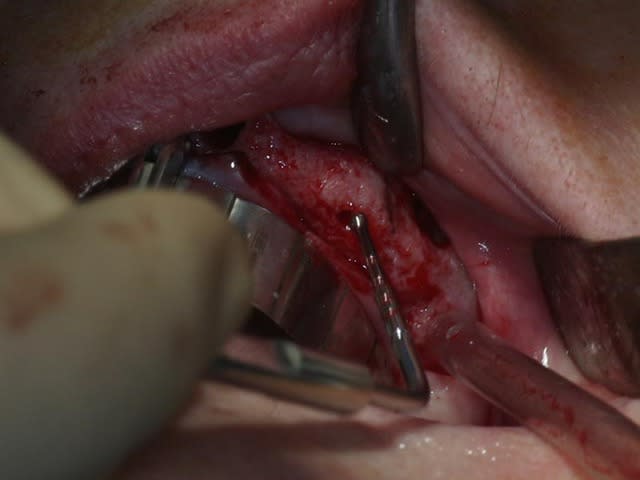

bon, toujours aussi speed je suis, mais après certaines réclamations, et malgrès ma réticence à poser un cas non "consolidé", voici en avant première mon premier all on 4, version photos ratées et non retouchées, mais... speed je suis je vous disais ;)

sto le bla bla, et pasons le diaporama... bon voyage au pays de la mise en charge immédiate totale au maxillaire de fille carole sur dame ginette, une patiente en or que j' adore, et pour qui je suis très très heureuse d' avoir pu réaliser cette chirurgie et la première étape prothétique.....